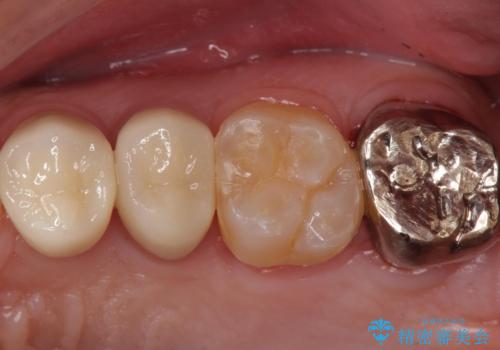

奥歯は十分な歯の高さがなかったため、クラウンをかぶせる前に歯周外科治療で歯の高さを出しています。

歯科に通うようになってから磨き残しの状態も改善されていきました。